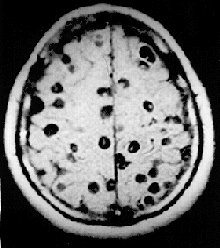

![]() Obraz neurocysticerkozy w MRI | |

Żywicielem pośrednim tasiemca uzbrojonego jest przeważnie świnia domowa, choć może być nim również dzik, niedźwiedź brunatny oraz niektóre małpy wąskonose i szerokonose. Zakażenie następuje drogą pokarmową, poprzez spożycie zakażonej wieprzowiny (lub mięsa innego zwierzęcia). Do ludzkiego mózgowia może jednorazowo przedostać się 1–2000 wągrów (czasem nawet więcej), które lokalizują głównie w korze mózgu (najczęściej w płatach czołowych i skroniowych oraz wzdłuż tętnicy środkowej mózgu). W mniejszych ilościach wągry zasiedlają także opony mózgowo-rdzeniowe i układ komorowy, a niekiedy również w pień mózgu. Liczebność larw pasożyta w organizmie wpływa na intensywność oraz przebieg choroby. W przeciwieństwie do rozsianej wągrzycy (cysticerkozy) mięśniowej, w neurocysticerkozie wągry nie otorbiają się. Cysticerkusy zlokalizowane w przestrzeni podpajęczynówkowej oraz komorze IV nazywają się cysticercus racemosus, a w ich wnętrzu znajdują się pęcherzyki (niezawierające skoleksów), których wzrost może przypominać przerzuty nowotworowe.

W 50% przypadków neurocysticerkoza przebiega bezobjawowo. U pozostałych pacjentów pierwsze objawy często pojawiają się dopiero po kilku latach od zakażenia. Do najbardziej typowych należą: drgawki (zwykle świadczą o zajęciu przez wągry komór mózgu, mogą prowadzić do stanu padaczkowego lub być sporadyczne), wzrost ciśnienia śródczaszkowego (zwykle świadczy o zajęciu przez wągry pnia mózgu, powoduje postępujące bóle głowy, wymioty, zaburzenia widzenia i niedowłady) oraz zaburzenia psychoorganiczne (wysuwające się z czasem na pierwszy plan, wyrażające się niepokojem lub spowolnieniem psychoruchowym, zaburzeniami orientacji, halucynacjami, a w bardziej zaawansowanych stadiach także apatią, amnezją lub demencją). W trakcie choroby występują zarówno okresy zaostrzeń objawów, jak i remisji, co ma najprawdopodobniej związek z obumieraniem pojedynczych wągrów.